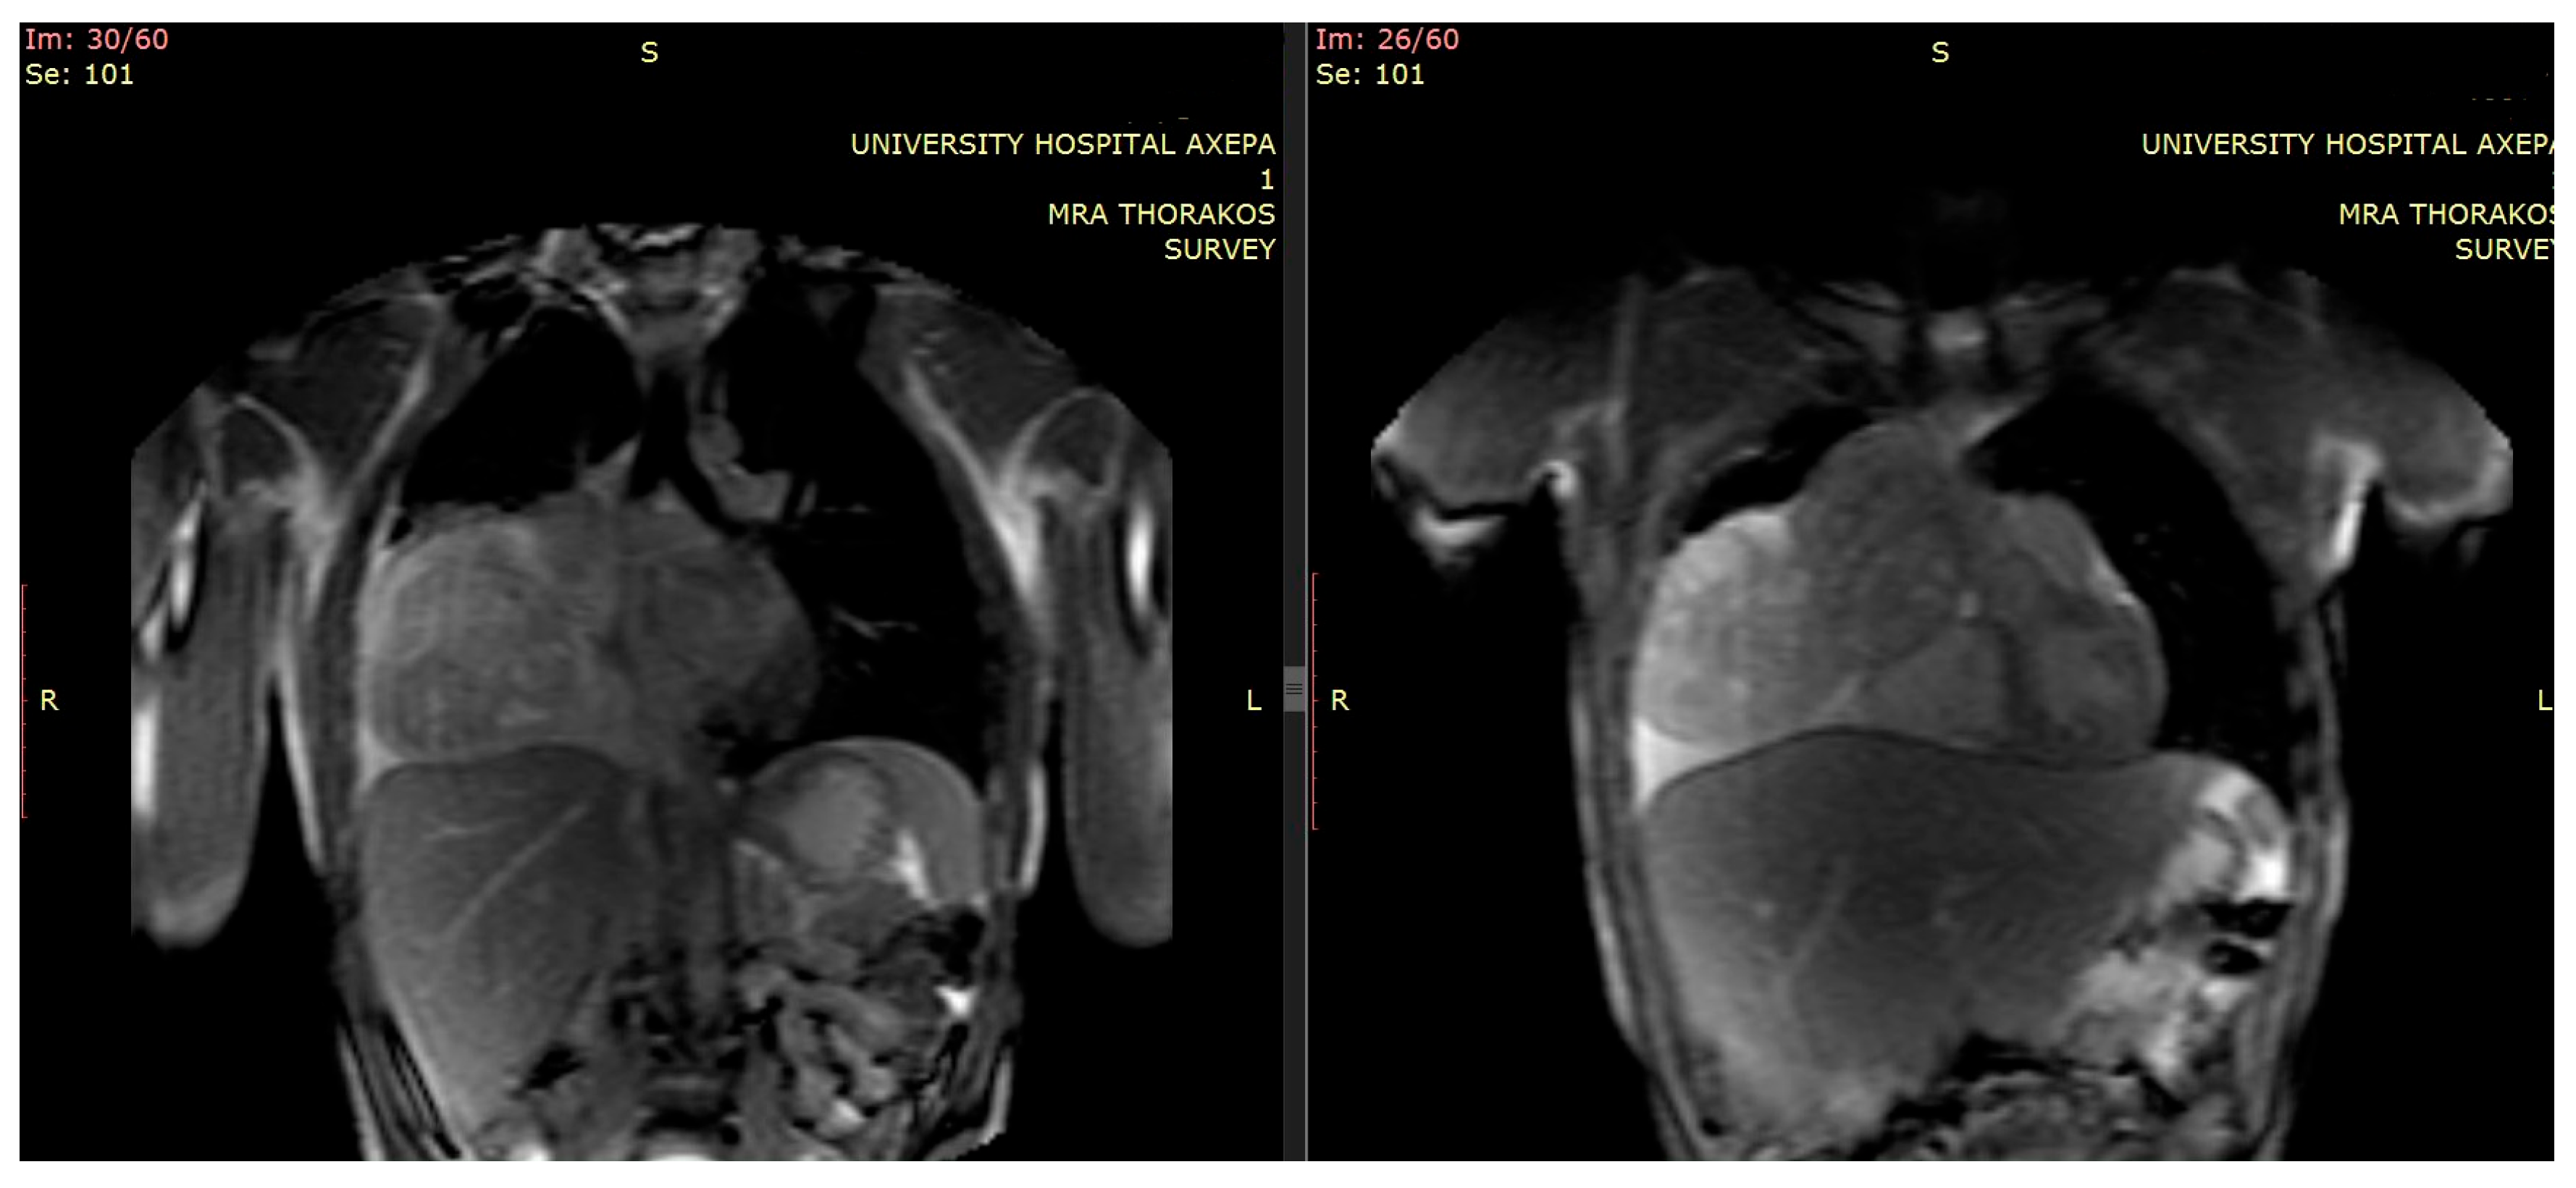

Furthermore, additional magnetic resonance imaging (MRI) provided details regarding local invasion, particularly about pericardial and vascular structures [5] (Figure 2).

The tumor’s measurements had increased (DMax: 16 cm × 9 cm × 13 cm). Intraoperatively, severe degree of atelectasis of the Right Lower Lobe (RLL) parenchyma with an additional pressure–displacement effect upon the Superior Vena Cava (SVC) and (R) heart sinus were detected. These findings were already indicated from the preoperatively performed chest MRI. Immediately postoperatively, the patient’s respiratory mechanics significantly improved, while the received tissue provided conditions for definitive histological classification and molecular analysis [10] (Figure 3).

Figure 2. Initial preoperative MRI.